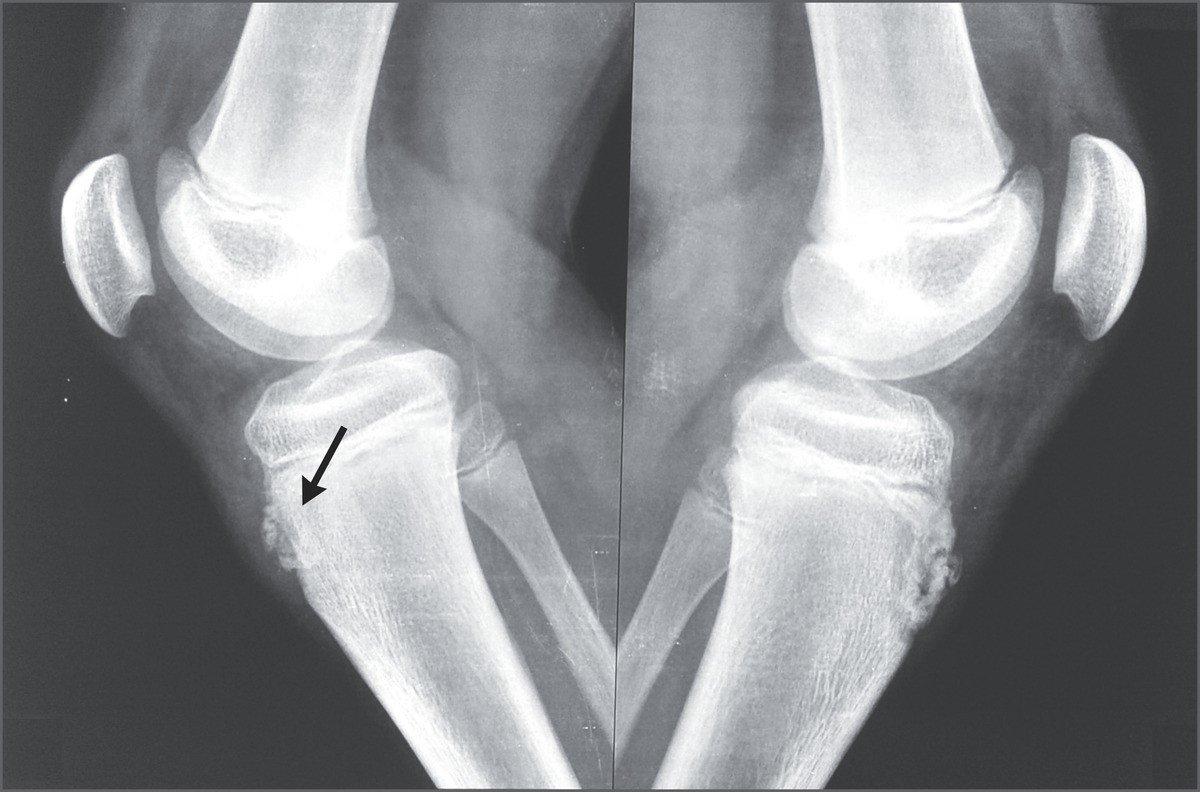

Source: boullakxs.pages.dev Morbus OsgoodSchlatter Heilpraxis , Gestern hatte ich dann einen Termin bei einem Orthopäden und nachdem er sich mein Röntgenbild angeschaut hat meinte er, ich hätte das sogenannte Morbus Osgood Schlatter in der Pubertät gehabt und daraus würde jetzt der Reizzustand Tuberositas tibiae resultieren. Hallo, Ich bin 18 und leide seit 4 Jahren an Morbus Schlatter